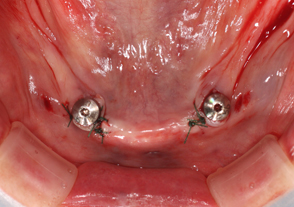

- ガイデットサージェリー手術

- インプラント埋入手術直後